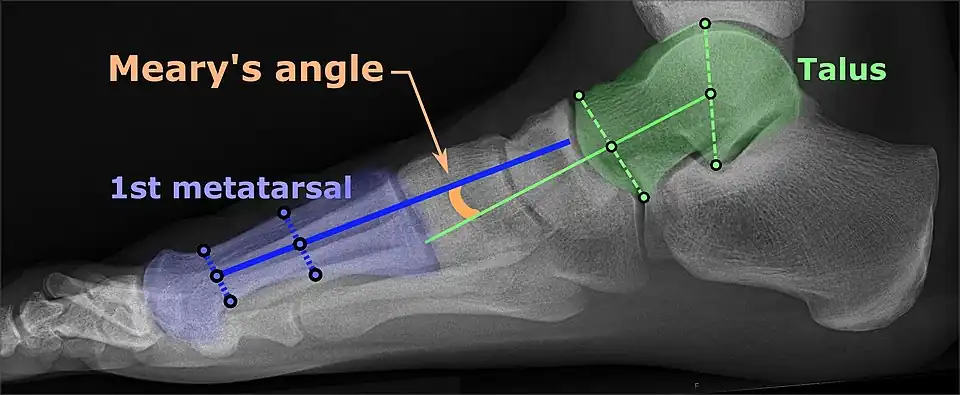

On weightbearing projectional radiography, pes cavus can be diagnosed and graded by several features, the most important being medial peritalar subluxation, increased calcaneal pitch (variable) and abnormal talar-1st metatarsal angle (Meary's angle).[17] Medial peritalar subluxation can be demonstrated by a medially rotated talonavicular coverage angle.[17]

Same lateral X-ray showing the measurement of Meary's angle, which is the angle between the long axis of the talus and first metatarsal bone.[17] This example is slightly convex downward. An angle greater than 4° convex upward is considered pes cavus.[17] -